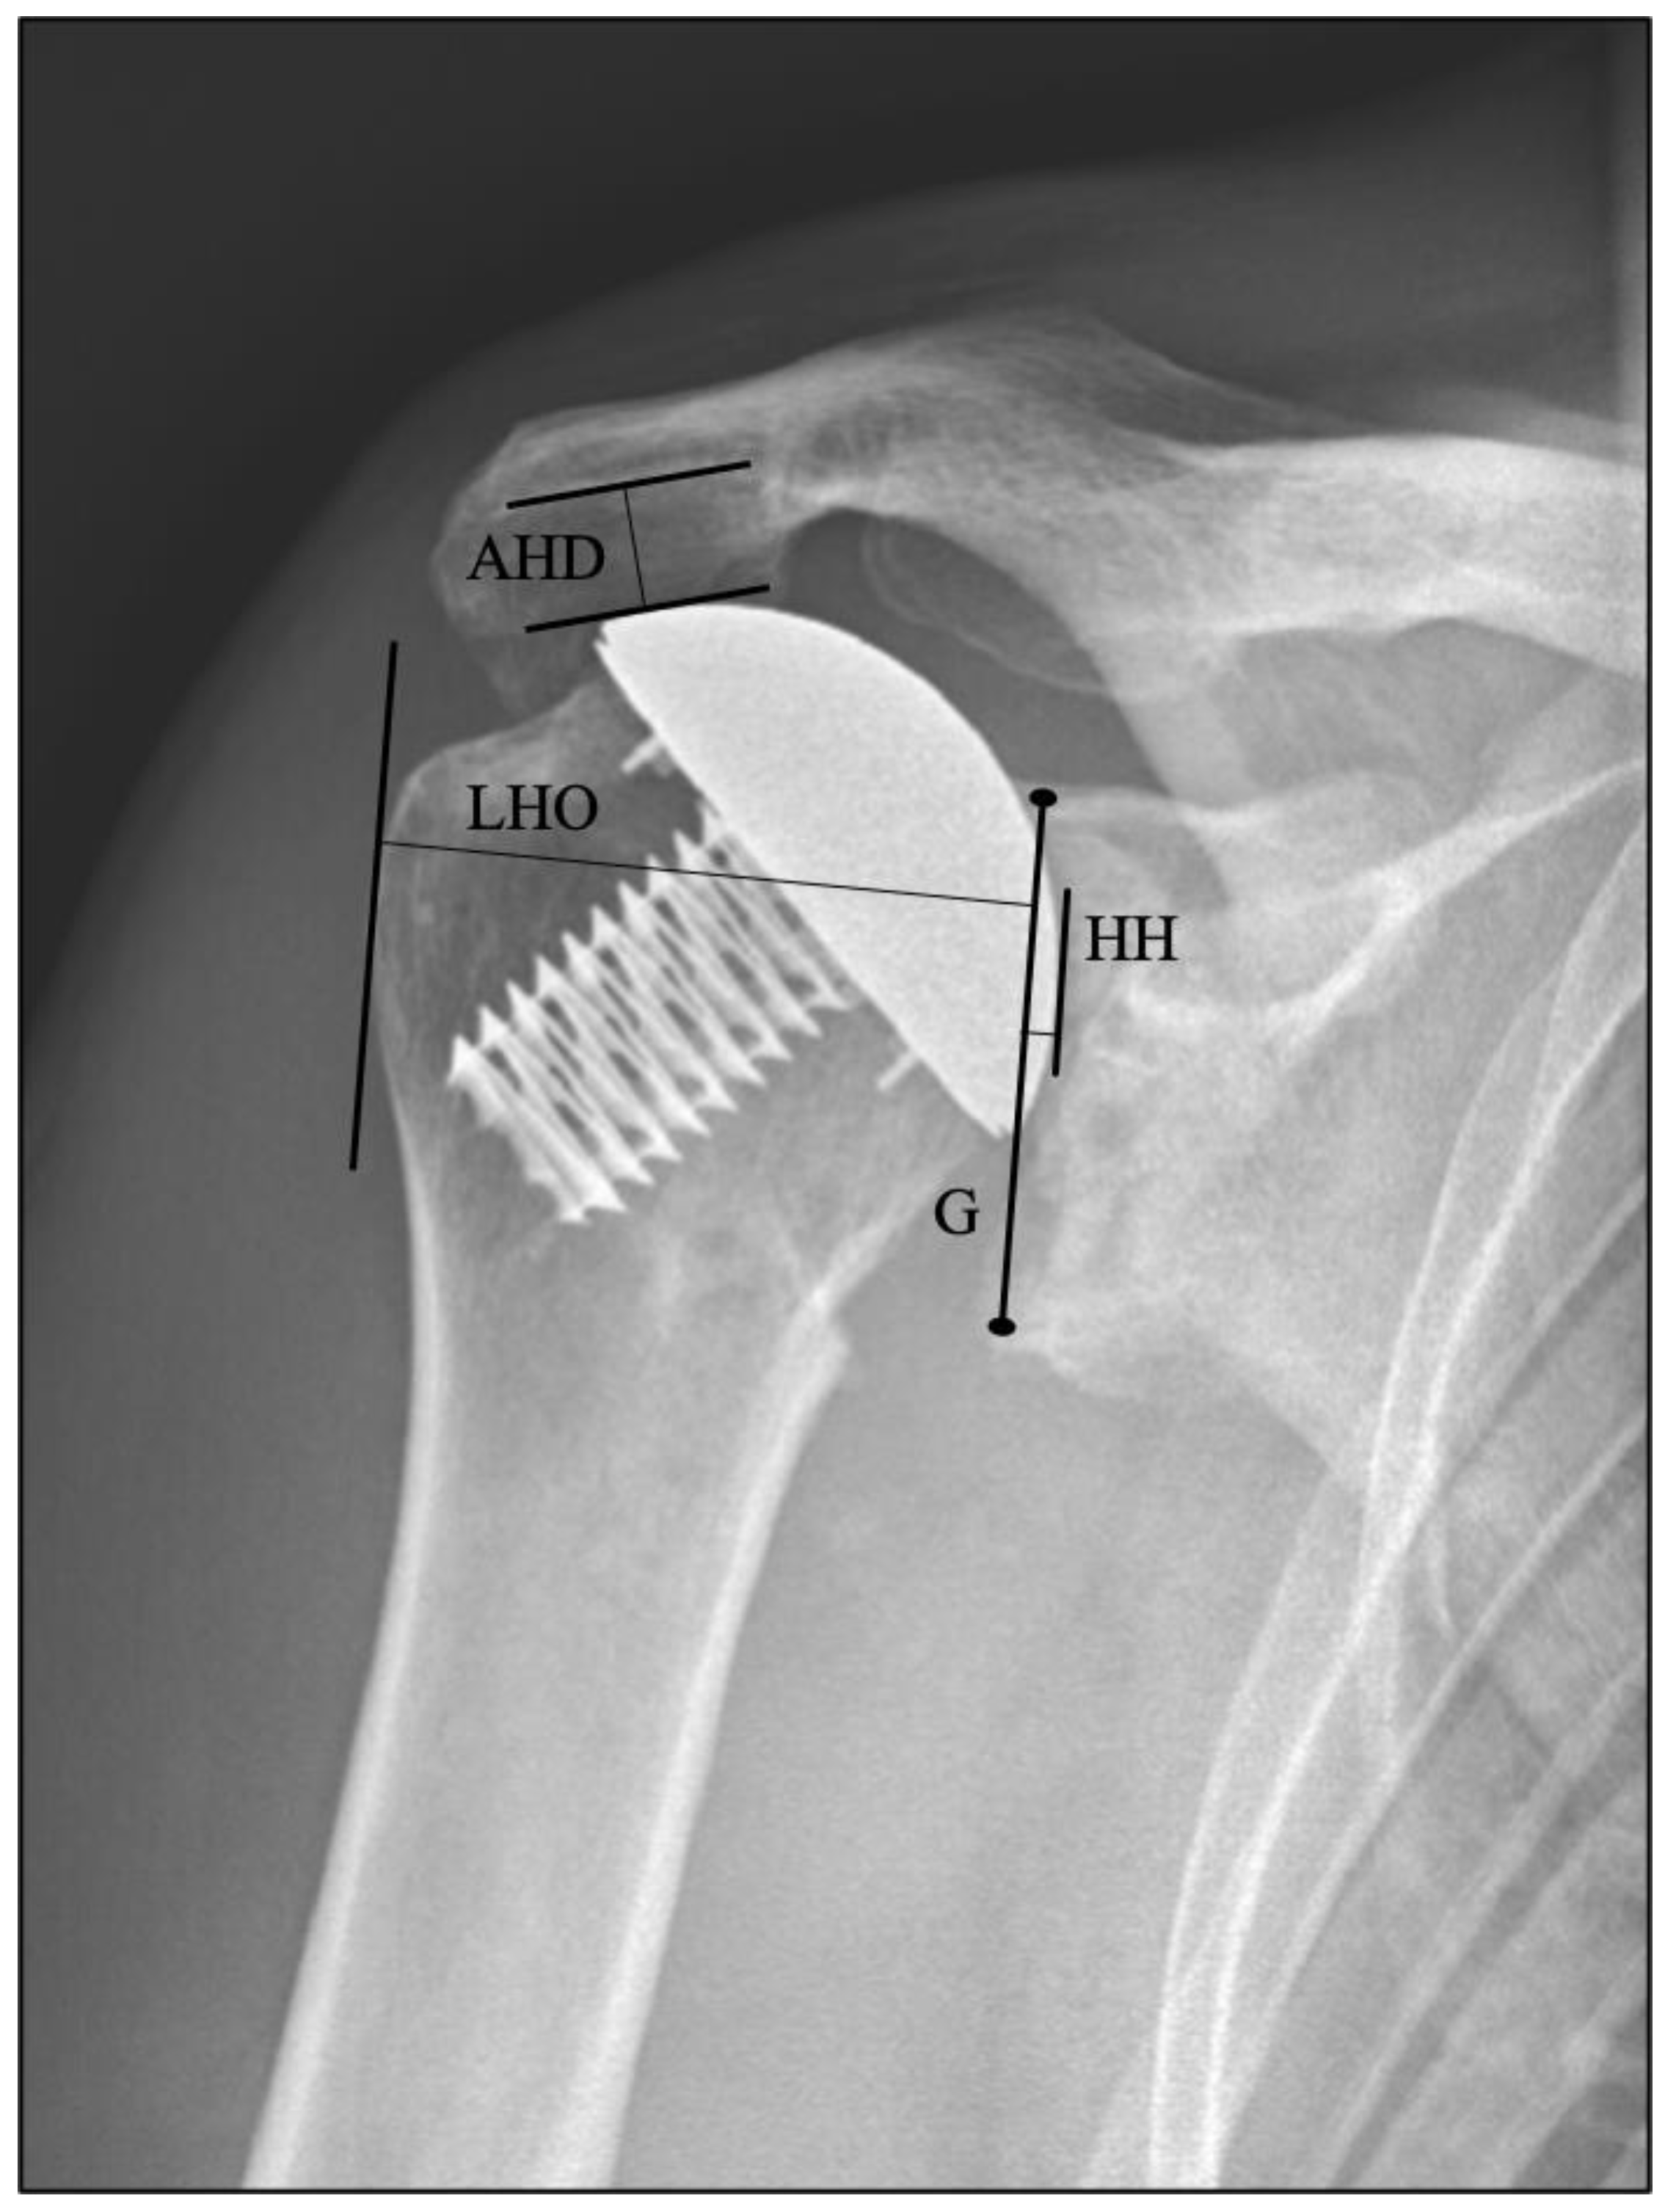

True anteroposterior (AP) and axillary radiographs were obtained postoperatively at each follow-up examination according to a standardized internal protocol using a calibrated digital tool for imaging visualization (JiveX VISUS Health IT GmbH, Germany). All measurements were evaluated on AP views with internal rotation (Figure 1). To grade radiolucent lines, both radiographic projections, axillary and AP, were considered. Radiolucency was graded on a scale from 0–5 according to the extent of radiolucent lines at the bone-cement interface from Lazarus et al. [19], adjusted for pegged glenoids and originally implemented by Franklin et al. in 1988 for keeled glenoids [17]. The average of the grades from axillary and AP radiographs resulted in the final grading. To detect a mediolateral shift, the following parameters were measured: lateral humeral offset (LHO) and joint gap width (JG). Acromiohumeral distance (AHD) was evaluated to detect potential cranialization of the humeral head. For the assessment of craniocaudal positioning of the humeral head on plain radiographs, the AHD is a commonly used and reliable measurement [26]. Parameters of radiographs were measured by the same examiner, an orthopedic resident with experience in musculoskeletal radiology, blinded to the clinical outcomes. Glenoid morphology classification according to Walch was based on axillary radiographs, since not every patient had a CT scan preoperatively [27].

Figure 1.

Anteroposterior measurements are illustrated on radiographs. The black line connects the superior and inferior rim of the glenoid (G) and is taken as the base for the joint gap width (black line to the right), which is the parallel line crossing the most medial part of the humeral head (HH) prosthesis. Positive values were given when the humeral head appeared more laterally relative to the drawn line, and negative values were given when more medially, respectively. The lateral humeral offset (LHO) is the distance (mm) measured from the drawn baseline to the parallel crossing the most lateral point of the greater tubercle. Acromiohumeral distance (AHD) is from the caudal point of the acromion perpendicular to the apex of the humeral head [28,29]. JG and LHO indicate a mediolateral shift of the humeral head, whereas the AHD represents cranialization.